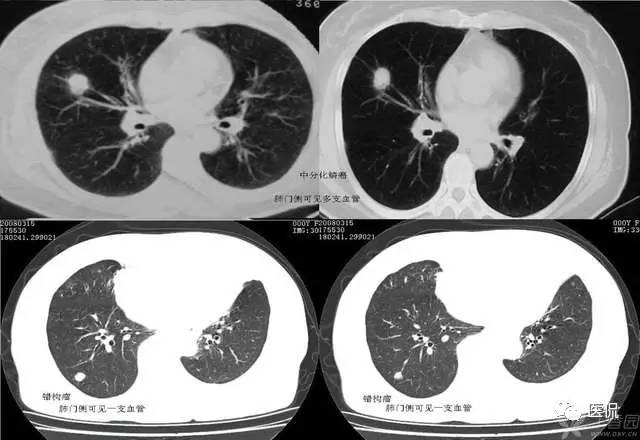

花朵征

花朵征这里主要指传染性非典型肺炎(SARS)的早期表现。该病早期CT表现较有特征性:肺窗上观察,肺血管纹理显著增强,一般在小叶范围渗出,主要为间质渗出,因此密度较淡,往往呈磨玻璃样密度,外形如“花朵”样,即增粗的血管纹理为“花柄”,小叶范围的渗出影像为“花冠”,散布其间的肺血管分支犹如“叶脉”,形成一朵朵根在肺门,朝向胸膜下的含苞欲放的“鲜花”,彼此界限清;病变严重时,“花朵”可融合,形成“花丛”样外观;纵隔窗上常不显影;纵隔淋巴结不大;早期空气支气管征不多见,进一步实变时明显;动态观察,进展迅速,但吸收慢,和临床症状不同步,后期纤维化明显;常在背部坠积性发病,而支气管开口向上的肺叶、段发病相对少见;可以以上肺野发病为主,此时较难与结核鉴别;有少数病人可出现胸腔积液,如治疗得当,吸收很快。典型病例大体可分为间质渗出期、实质渗出期和纤维化期三期。

SARS病毒是一种新病毒,与常见的引起呼吸道感染的其他病毒相比,其毒力强,致病力强,人群普遍易感,因此很容易引起肺部炎症;但其也与其他病毒有共性,早期往往为间质性肺炎,具有间质性肺炎的一般特点。但SARS病毒引起的肺炎,其病理变化较其他常见病毒性肺炎更剧烈,常迅速。造成明显的肺部渗出。发病早期,以间质渗出为主,病毒短时间内大量繁殖,引起血管周围间质及小叶间质渗出,肺泡腔内只有少量的液体和细胞成分,因此病灶密度较淡;肺部明显充血,血管纹理显著增强,以增强的血管纹理为中心,形成“花朵”征或“花丛”征,大体与肺动脉的供血区域形态一致;病变进一步进展时,可有明显的肺泡渗出,从而演变为实质炎,病灶密度增高。此时病理上可见肺泡腔内有大量细胞成分,有时可见透明膜,红细胞。经过治疗后,渗出减轻,部分吸收,肺泡的渗出相对容易吸收,而间质的渗出吸收较慢,容易引起肺间质纤维化,此时病人的自觉症状多数已明显改善,体温业已降为正常,病灶相对静止,可长时间存在肺部阴影。若渗出过多,吸收不良,持续影响通气、换气功能,则可因严重缺氧、呼吸衰竭而导致死亡。由于本病无化脓倾向,因此,整个病程未出现肺实质结构的坏死与破坏,所以也没有形成空洞,这容易和结核鉴别;本病亦少累及大气道,纵隔、肺门淋巴结也不大,因此,一般不引起肺不张,咳嗽、咳痰也较不明显,这与常见的细菌感染引起的实质炎明显不同。可以说,早期非典的CT表现是典型的。

传染性非典型肺炎(SARS)常为双肺发病;多位于两肺中下野胸膜下周边带,但与胸膜之间常有透亮带,较少累及叶间裂或段间裂,不以明确的叶或段分布。